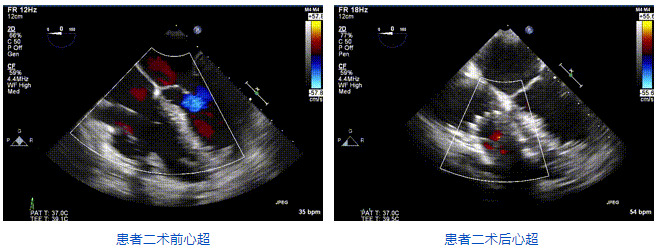

本周三例接受LuX-Valve Plus經(jīng)血管三尖瓣置換術(shù)的患者中,第一例患者為冠狀動脈旁路移植術(shù)+Bentall+二尖瓣成形術(shù)后;第二例患者為永久起搏器植入術(shù)后,存在跨三尖瓣導(dǎo)線;第三例患者合并房顫、房缺及左心耳封堵術(shù)后。

三例患者入院后,葛均波院士團(tuán)隊周達(dá)新教授、潘文志教授、張源博士、陳莎莎博士及心超室的潘翠珍教授、李偉教授對患者的情況進(jìn)行詳細(xì)評估和討論,最終決定為三例患者選擇LuX-Valve Plus40mm、50mm和50mm型號的瓣膜進(jìn)行手術(shù)治療。手術(shù)后即刻拔除氣管插管,術(shù)后患者三尖瓣反流癥狀得到顯著改善,復(fù)查心超結(jié)果顯示人工三尖瓣瓣膜支架固定穩(wěn)定,瓣葉關(guān)閉形態(tài)未見異常,未見明顯反流。